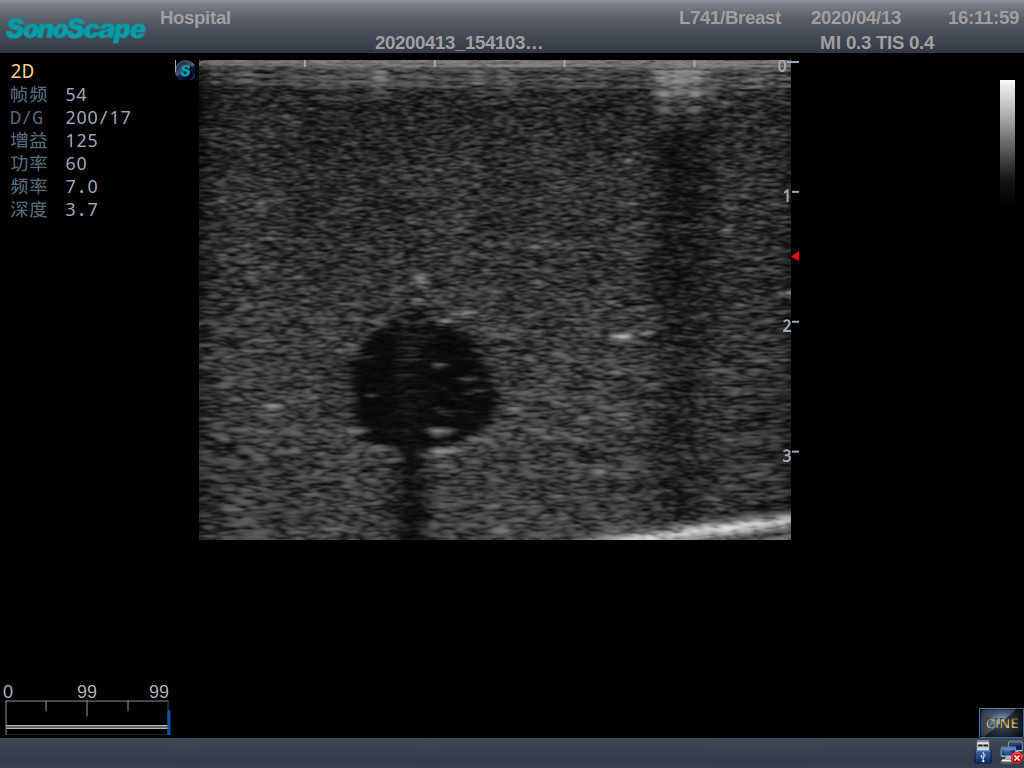

4) Biomimetic material allowing users to see clear and real normal tissues and space-occupying lesions that are hyperechoic, hypoechoic and isoechoic as they would see in the clinical environment